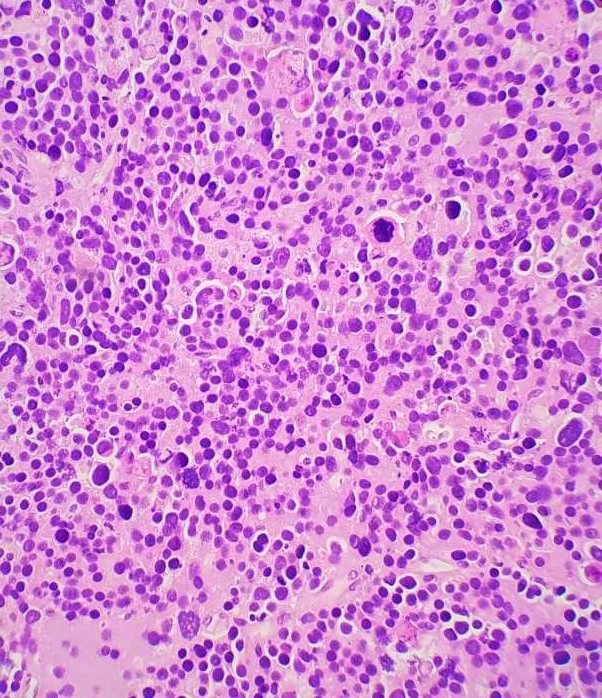

Spermatocytic tumor is a rare germ cell tumor (1-2%) with an average patient age of 55 but does occur in younger individuals such as in this case. Patients often present with testicular swelling with mass. Serum tumor markers are generally not elevated. Macroscopically, these tumors appear as a well-circumscribed tan-grey mass with a bulging surface. Microscopically, these tumors demonstrate a diffuse or sheet-like pattern with edematous stroma and separation by fibrous bands. The tumor is comprised of a polymorphous cell population comprised of 3 main cell types: Small lymphocyte-like cells, intermediate cells and giant cells. Germ cell neoplasia is usually not associated with spermatocytic tumors. The tumor cells are positive for SALL4, CD117, OCT2, CAM 5.2 (40%), and negative for CD30, PLAP, AFP, OCT3/4, D2-40, Glypican-3, EMA, CD30 and Vimentin. The differential diagnosis includes seminoma, embryonal carcinoma (solid pattern) and malignant lymphoma. Radical inguinal orchiectomy is curative with an excellent prognosis.